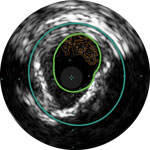

Lumen with fresh thrombus

Micro-calcification

Calcified plaque with acoustic shadowing

Vessel size: 6 mm diameter Plaque morphology: Mixed, thrombic plaque with medial calcium Plaque geometry: Eccentric lesion Guidewire position: True lumen

Quick-Cross catheter: Confidently cross challenging morphologies Turbo-Power laser atherectomy: Forward facing directional debulking to clear thrombus; rotation for improved deliverability in calcified lesions AngioSculpt scoring balloon: Safely dilate residual stenosis4 Stellarex DCB: Designed for performance in calcium